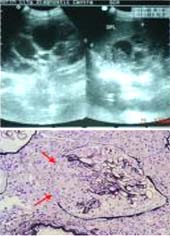

Một số hình ảnh trên bệnh nhân SD/SXHD qua siêu âm

Trong y văn một số tác giả trong và ngoài nước gần đay có đề cập các triệu chứng, dấu chứng hoặc hình ảnh do biến chứng của bệnh SD/SXHD gây ra, đó có thể là dấu chứngư, biến chứng nặng; đổng thời, các chỉ điểm dày vách túi mật, tràn dịch đa màng, gan lách lớn nhanh, vỡ thận, tụy lớn nhanh,…như thế có thể xem như yếu tố tiên lượng diễn biến bệnh (mức độ nặng) của bệnh nhân trong khía cạnh thực hành lâm sàng hoặc đánh giá độ nặng và chuyển độ nặng vào sốc. Theo phân tích của Setiawan (1998) có mô tả về các hình ảnh như thế và qua nghiên cứu 16 trường hợp (15 người lớn và 1 trẻ em) tại Trung tâm chẩn đoán y khoa Medic, bước đầu chỉ mới chẩn đoán kịp thời SXHD, nhập viện điều trị chứ chưa ghi nhân được trường hợp nào có chuyển độ hay không ? Hoặc nghiên cứu của BV Bệnh nhiệt đới thành phố Hồ Chí Minh, BV Nhi đồng Cần Thơxác định các dấu hiệu dày thành túi mật, dịch dưới bao gan, dịch ổ bụng và dịch màng phổi trên siêu âm và tìm sự liên hệ giữa siêu âm cũng như tiên lượng sốc trong sốt xuất huyết độ I, II rất có ý nghĩa,…Y văn trong và ngoài nước phần lớn chỉ nghiên cứu trên trẻ em. Y văn trong nước rất hạn chế về số ca mô tả và công bố về thay đổi mô tuỵ, tăng men tuỵ gây đau vùng thượng vị, vỡ thận tự phát. Nhân đây, chúng tôi tổng hợp một số thông tin liên quan đến một số hình ảnh được xác định qua siêu âm và nội soi tiêu hóa trong các ca SD/SXHD.

Dày vách túi mật:

Thuật ngữ này đã có tác giả gọi là viêm túi mật không sỏi (Van Troys, 2000), là yếu tố tiênlượng dự hậu. Theo Setiawan, dày vách túi mật 3-5 mm là tiêu chuẩn chỉ định nhập viện và theo dõi, dày trên 5mm là tiêu chuẩn cho bệnh nhân nguy cơ cao vào sốc giảm thể tích. Kim Y.O và cộng sự (2000) nhận thấy dày vách túi mật thường liên quan đến hội chứng thận trong sốt xuất huyết do Hantavirus. Theo nghiên cứu của tác giả Trần Thị Hữu Trí và cộng sự (2007) tại BV Nhi đồng Cần Thơ, trong 38 trường hợp có 19 trường hợp rơi vào sốc(chuyển độ), thường bệnh nhi rơi vào sốc là ngày thứ 4-5 chủa bệnh (chiếm 52.7%) và tỷ lệ vào sốc ngày thứ 6 cũng cao (42%), trong đó dấu hiệu dày thành túi mật ở những trường hợp chuyển độ(sốc) là 77.3%.

Gan to, lách to và dấu hiệu dịch dưới bao gan

Trong nhóm SXHD độ III-IV, thường có tụ dịch quanh thận và cạnh thận trong 77% trườnghợp, tụ dịch dưới bao gan và lách 9% trường hợp, tràn dịch màng tim 8% trường hợp (Setiawan). Trong một nghiên cứu cũng được tiến hành bởi nhóm Trần Thị Hữu Trí và cộng sự (2007) cho thấy tỷ lệ dấu hiệu tụ dịch bao gan ở nhóm trẻ sốt xuất huyết chuyển độ (sốc) là 78.6%. Những trường hợp SXH có vào sốc đa phần có dịch dưới bao gan (78.6) và ngươc lại SXH không sốc có dịch dưới bao gan chiếm tỷ lệ ít hơn (21.4%). Điều đó có nghĩa là những bệnh nhi khi siêu âm bụng có dấu hiệu “dịch dưới bao gan” thì nguy cơ vào sốc cao hơn những trẻ không có dấu hiệu này trên siêu âm bụng. Đặc biệt trong một số ca có biểu hiện viêm gan, tăng men gan SGOT và SGPT gấp nhiều lần, có/ không kèm theo vàng da hoặc suy gan cấp, có thể khi đó virus Dengue đã trực tiếp xâm nhập, gây tổn thương tế bào gan và tế bào Kuffer, có thể liên quan đến chảy máu tự phát; khi đó, siêu âm thấy gan và lách tõ ra rõ.

Dịch ổ bụng:

Thường xảy ra trong sốt xuất huyết đã được ghi nhận từ những năm 90 (Pramuljo). Trongnhóm SXHD độ III-IV, thường có tụ dịch quanh thận và cạnh thận trong 77% trường hợp, tụ dịch dưới bao gan và lách 9% trường hợp, tràn dịch màng tim 8% trường hợp (Setiawan). Khoảng 80% số ca SXHD có sốc có dịch ổ bụng và chỉ có 20% trường hợp SXH không sốc có dịch ổ bụng, sự khác biệt này có ý nghĩa thống kê qua nghiên cứu (Trần Thị Hữu Trí và cs, 2007). Điều này có nghĩa là ca SXHD khi siêu âm nếu có dấu hiệu dịch ổ bụng thì nguy cơ vào sốc cao hơn nhóm không có dịch ổ bụng. Nên dấu hiệu “dịch ổ bụng” có giá trị tiên đoán sốc.

Tràn dịch màng phổi (P) và (T) hoặc chỉ bên (P)

Trong thực tế lâm sàng về chẩn đoán hình ảnh, các chuyên gia cho biết chưa phát hiện tràn dịch màng phổi đơn thuần bên (T) (Pramuljo, 1991). Tràn dịch màng phổi (P) và tụ dịch dưới bao gan là yếu tố tiên lượng chuyển độ SXHD vào sốc. Tỷ lệ dấu hiệu tràn dịch màng phổi ở nhóm trẻ SXHD chuyển độ là 100%. Trong đó có 6 ca SXHD có dịch màng phổi chiếm tỷ lệ 15.8% nhưng cả 6 ca này đều rơi vào sốc (100%). Có nghĩa là nhóm có dịch mang phổi thì nguy cơ vào sốc cao và có thể đây là chỉ điểm có giá trị tiên đoán sốc cao.

Siêu âm khảo sát tốt dày vách túi mật, dịch màng phổi, dịch màng bụng, điều này có giá trị tiên lượng vào sốc ở các nhân SD/SXHD, nhất là bệnh nhân nhi SXHD nhằm theo dõi bệnh sát hơn để có biện pháp điều trị kịp thời. Trong mùa dịch, đứng trước những bệnh nhân có sốt kéo dài khi siêu âm thấy những dấu hiệu trên cần kết hợp lâm sàng để có định hướng chẩn đoán và chỉ định thêm xét nghiệm máu để chẩn đoán chính xác SXHD.

Đặc biệt, đối với bệnh nhi, những trường hợp có dấu hiệu chuyển độ vào sốc (độ II và III), đánh giá dựa trên các dấu hiệu dày vách túi mật, dịch màng phổi, dịch ổ bụng và tụ dịch dưới bao gan có giá trị tiên lượng rất tốt. Hiện tại, siêu âm là một phương tiện chẩn đoán dường như rất phổ biến ở các tuyến từ trung ương đến tuyến huyện, khi đã chẩn đoán ca bệnh là sót xuất huyết Dengue (theo tiêu chuẩn của WHO) rồi thì nên chỉ định làm siêu âm bụng tổng quát, nhằm phát hiện các chỉ điểm trên để tiên đoán bệnh nhân tốt hơn. Nội soi tiêu hóa trên phát hiện các vị trí và mức độ xuất huyết tiêu hóa trong SXHD có giá trị chẩn đoán, xử trí kịp thời các bệnh nhân, nhất là các bệnh nhân nặng.